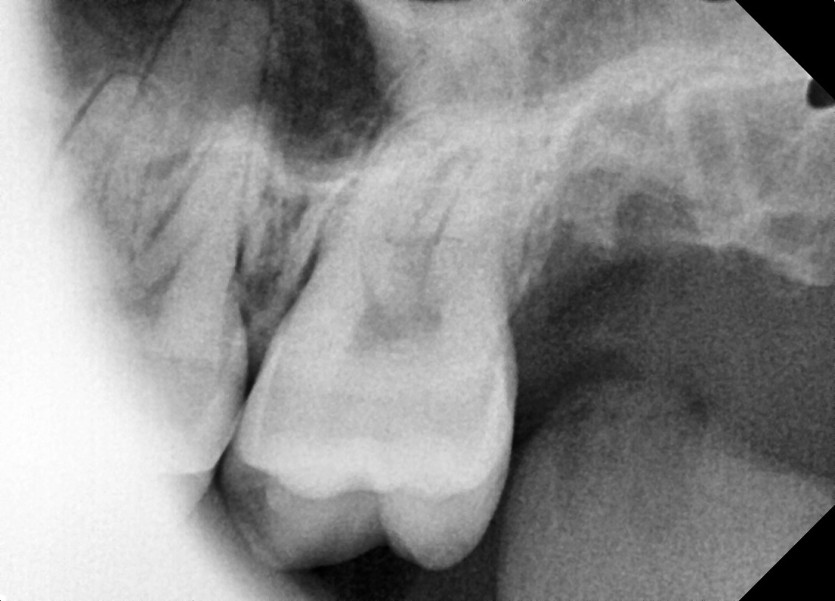

#28,38 사랑니 발치

구강 외과 전문의가 당일 발치했습니다.